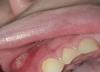

Что делать, если у ребенка болячка на десне: фото и советы

Дочь сегодня начала жаловаться на десну, что там болячка, сначала просто посмотрела, ничего такого не увидела

А сейчас снова мне она показала, я таком шоке, что это? Куда бежать? К кому бежать? Чем вообще такое обрабатывать?

Фото отправлю в комментарии